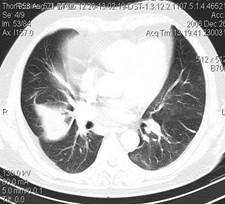

Больная В., 47 лет, находилась в гинекологическом отделении, где оперирована по поводу фибромиомы матки. Послеоперационный период осложнился тромбофлебитом глубоких вен левой нижней конечности. Через 10 дней после операции состояние больной внезапно ухудшилось, появилась одышка, боль в грудной клетке, кровохарканье. При осмотре: состояние средней степени тяжести. Отечность левой голени. ЧДД до 28 дыхательных движений в минуту, одышка усиливается при переходе пациентки в вертикальное положение. При перкуссии легких: легочный звук. Аускультация легких: везикулярное дыхание. Пульс 120 в минуту, ритмичен. Тоны сердца звучные, чистые. Усиление II тона над легочной артерией. АД 100/70 мм рт.ст. Живот при пальпации мягкий, безболезненный. Печень и селезенка не увеличены. Физиологические отправления в норме. Температура тела 37, 1°С. Анализ крови: Нв – 120 г/л, Эр- 4, 6 ·10 12/л, Лц – 9, 9·109/л, эозинофилы-1%, юные – 2%, палочкоядерные –18%, сегментоядерные –59%, лимфоциты – 22%, моноциты –6%, СОЭ – 20 мм/час. Анализ мочи без патологии. Протромбиновый индекс 98%. Время свертывания 2 мин. 10 сек. ЭКГ: синусовая тахикардия, отклонение ЭОС вправо. Глубокие зубцы SI, QIII; ТIII (отрицательный). В правых грудных отведениях картина блокады правой ножки пучка Гиса.

Компьютерная томография грудной клетки Больной В., 47 лет.

КТ – ангиография Больной В., 47 лет.